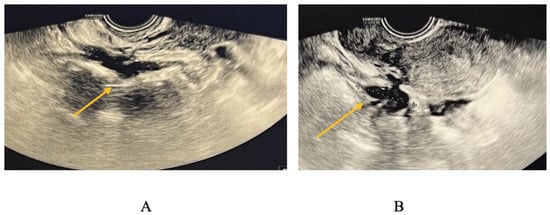

TVS is a reliable diagnostic tool for ovarian endometriomas (OMA), which can be readily identified due to their characteristic ground-glass appearance, which lacks any discernible vascular echo when assessed with a Doppler flow scanner, as depicted in Figure 3 [9,10].

TVS is employed to diagnose bowel DIE by recognizing the thickening of the intestinal wall in a solid or plaque-like approach, as well as the absence of visceral fat separating the recto-sigmoid and the uterine wall [17,18]. The findings are depicted in Figure 6, where the yellow arrow highlights the existence of a rectal nodule exhibiting a negative “sliding sign” and the asterisks indicate the length of the lesion. This sign denotes the absence of rectal mobility in relation to the uterus and the posterior vaginal fornix, suggesting the likelihood of adhesion and endometriosis lesions [17,18]. The adherence of the rectal DIE nodule to the uterine torus is illustrated in Figure 6B.

Figure 6. (A) TVS aspect of rectal endometriosis lesion, (B) TVS aspect of rectal endometriosis lesion adherent to uterine torus endometriosis lesion.